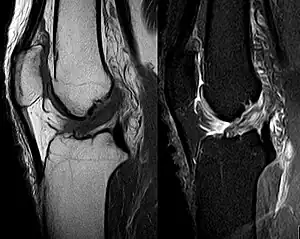

Though clinical examination in experienced hands can be accurate, the diagnosis is usually confirmed by magnetic resonance imaging, which provides images of the soft tissues like ligaments and cartilage around the knee.[1] It may also permit visualization of other structures which may have been coincidentally involved, such as the menisci or collateral ligaments.[30] An x-ray may be performed in addition to evaluate whether one of the bones in the knee joint was broken during the injury.[9]

MRI is perhaps the most used technique for diagnosing the state of the ACL, but it is not always the most reliable technique as the ACL can be obscured by blood that fills the joint after an injury.[31]

MRI is particularly useful in cases of partial tear of the ACL. The anteromedial band is most commonly injured compared to the posterolateral band.[32]